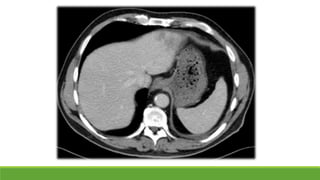

Amebiasis

◦ Amebiasis extraintestinal: absceso hepático, peritonitis,

absceso pleuropulmonar, lesiones cutáneas y genitales

Diagnóstico

◦ Quistes en heces formadas

◦ Trofozoítos en heces diarreicas

◦ Ac, Ag, PCR

Tratamiento

◦ Metronidazol 500-750 mg/8h 7 días  Paromomicina 500

mg/8h 7 días

Amebiasis Entamoeba histolytica Prevalencia muyvariable: 1-28 % Clínica ◦ Asintomático ◦ Amebiasis intestinal: disentería, colitis, apendicitis, megacolon tóxico ◦ Amebiasis extraintestinal: absceso hepático, peritonitis, absceso pleuropulmonar, lesiones cutáneas y genitales Diagnóstico ◦ Quistes en heces formadas ◦ Trofozoítos en heces diarreicas ◦ Ac, Ag, PCR Tratamiento ◦ Metronidazol 500-750 mg/8h 7 días  Paromomicina 500 mg/8h 7 días